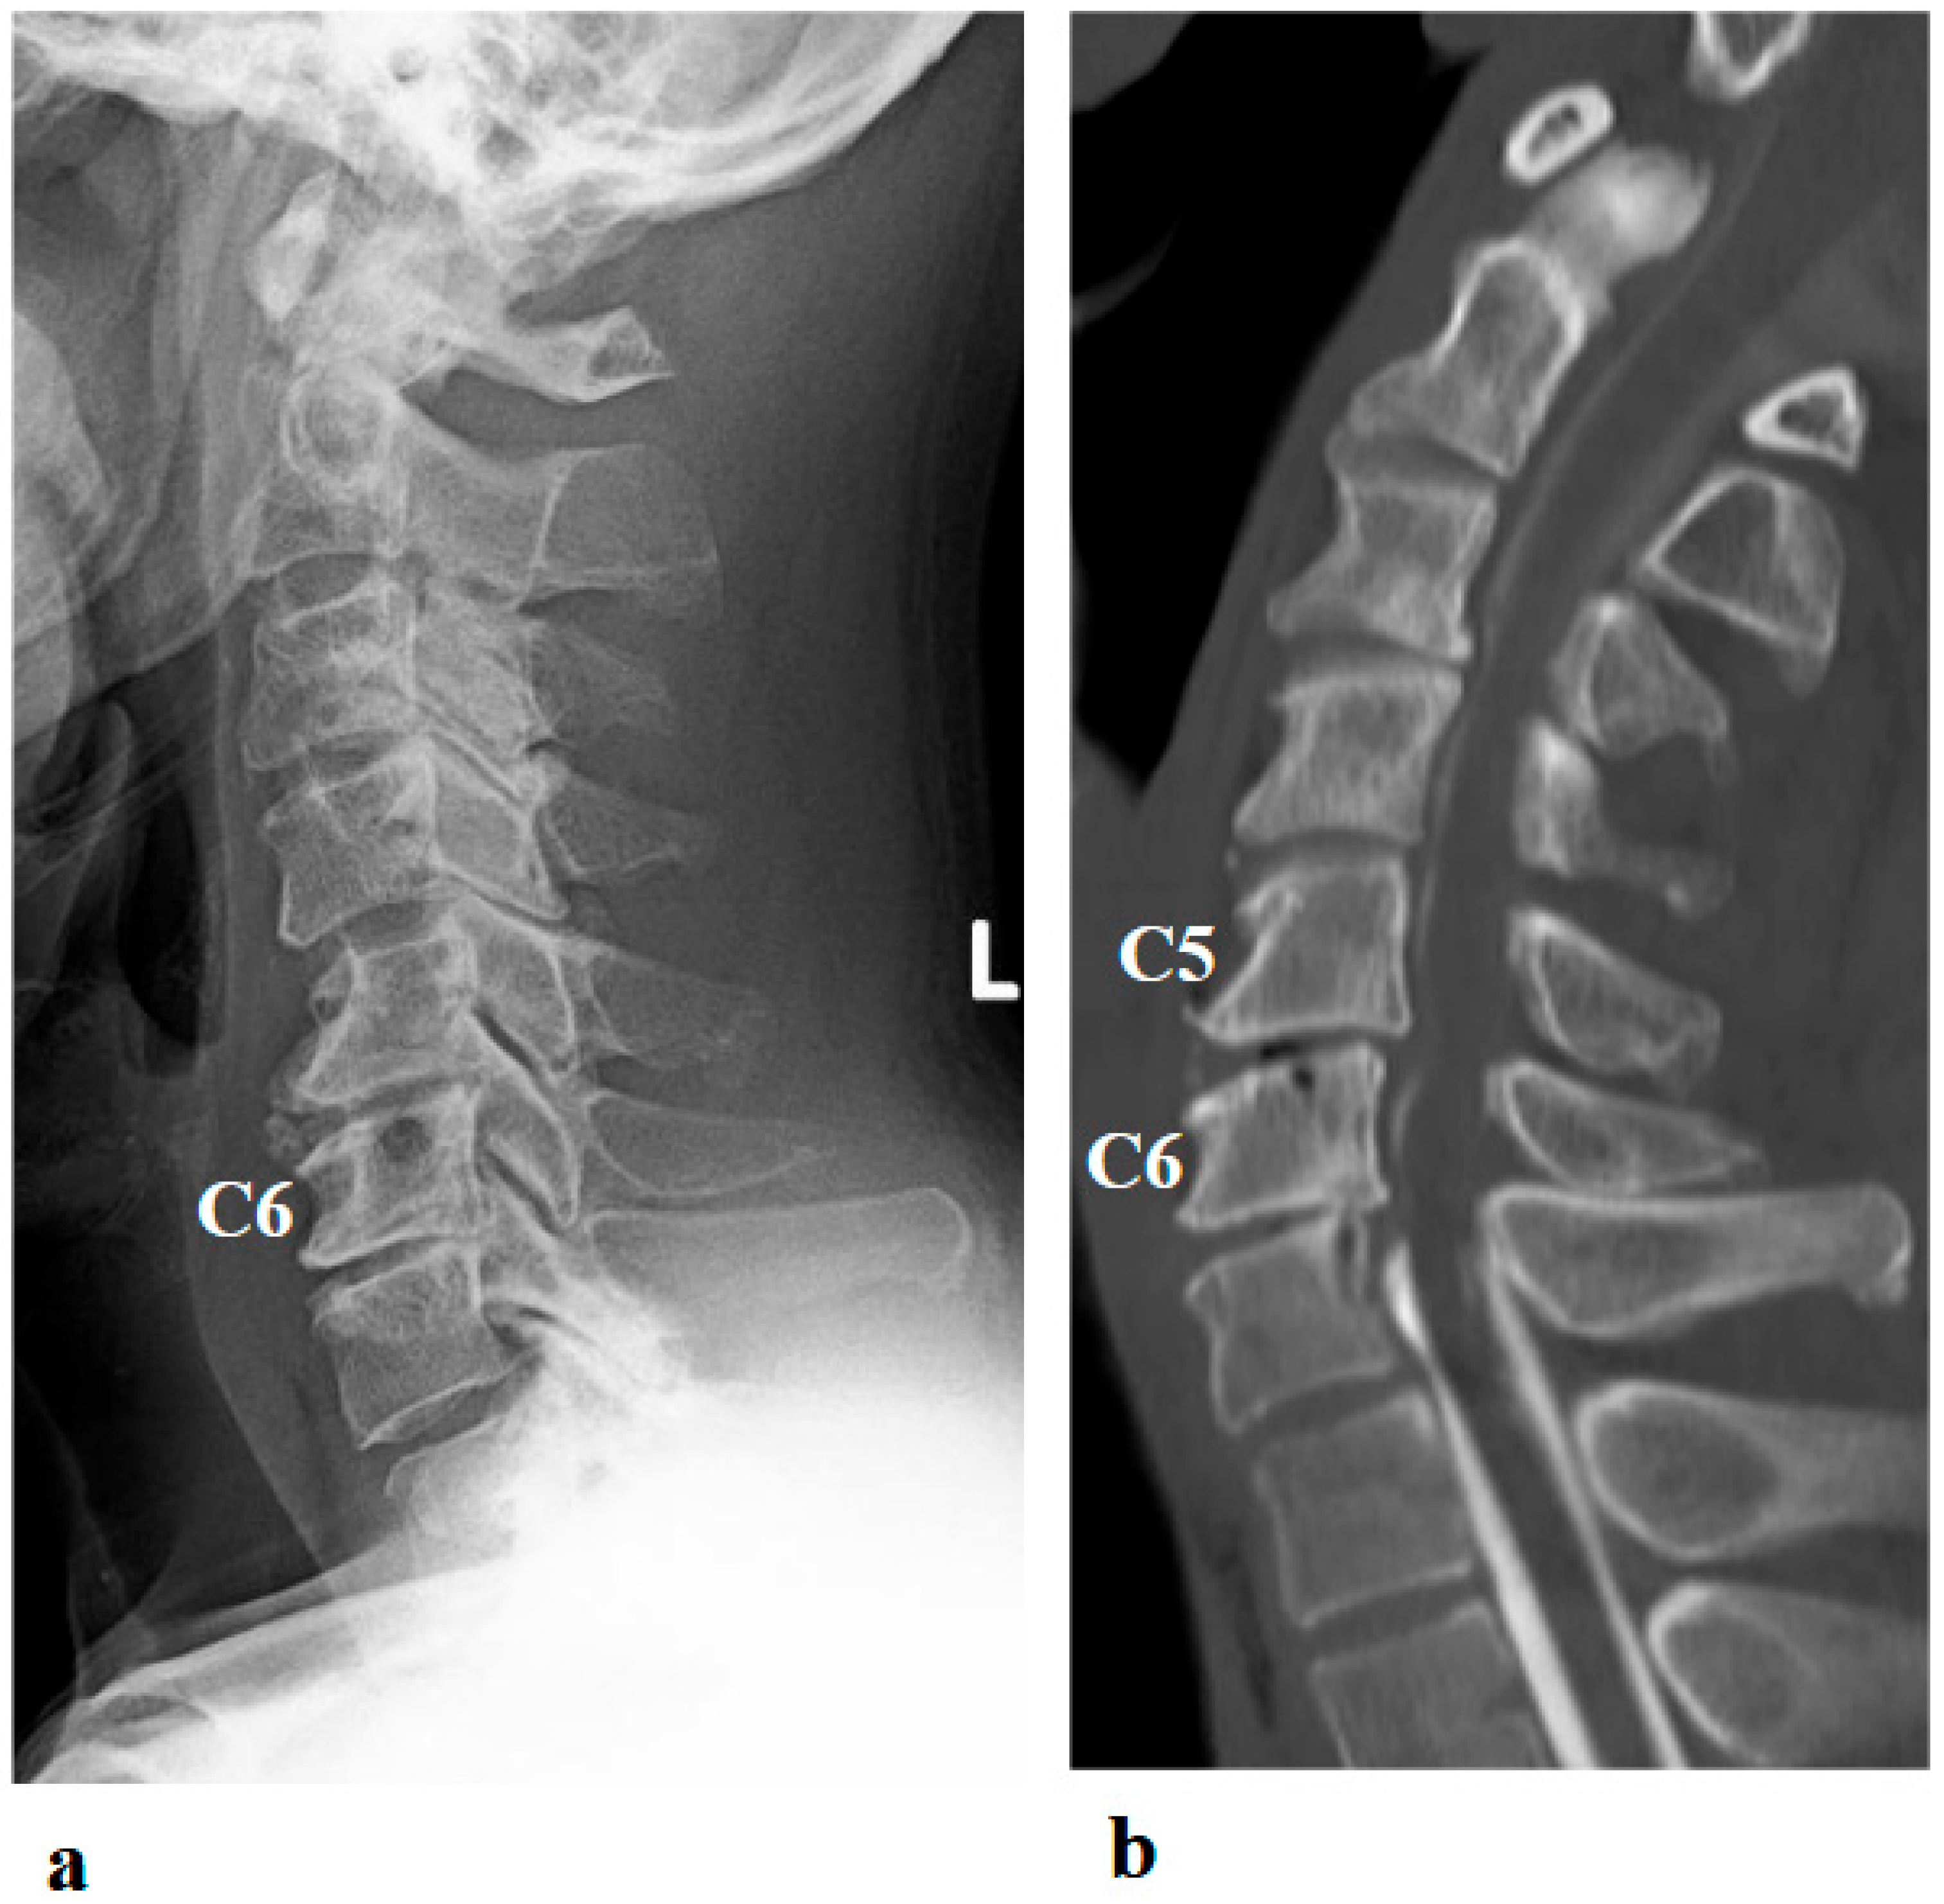

A 46-year-old man presented to the outpatient clinic of our hospital with a chief complaint of right-sided C5 palsy that had persisted for 41 months following cervical spine surgery (Figure 1). At the age of 43, he noticed a decrease in grip strength in his right hand and numbness in his right upper limb, and visited another hospital. Examinations at that hospital revealed that his initial symptoms were caused by cervical spondylotic myelopathy due to spinal cord compression from degenerative cervical vertebrae (Figure 2a,b). Based on the diagnosis, at that hospital, he underwent anterior decompression and fusion surgery at the C5–C6 level (Figure 2c). Prior to initiation of HAL therapy at our hospital, his neurological assessment was as follows: Numerical Rating Scale for pain = 4, American Spinal Injury Association (ASIA) motor score = 97, and ASIA sensory score = 108.

Figure 2.

Preoperative (a,b) and postoperative (c,d) images following the first surgery, as well as postoperative images from the second surgery (e–g). (a) Lateral cervical spine X-ray showing narrowing of the intervertebral disc space and osteophyte formation at C5–C6 and C6–C7. (b) Reconstructed mid-sagittal CT image after myelography revealing spinal cord compression at C5–C6 and C6–C7, and posterior displacement of the C5 vertebral body. (c) Postoperative lateral cervical spine X-ray after anterior decompression and fusion at C5–C6. (d) Mid-sagittal cervical MRI demonstrating persistent spinal cord compression from C3–C4 to C6–C7. (e) Postoperative lateral cervical spine X-ray after C4–C6 laminoplasty and partial laminectomy at the caudal aspect of C3 and the cranial aspect of C7. (f) Mid-sagittal cervical MRI showing adequate spinal cord decompression from C3–C4 to C6–C7. (g) Axial CT image at the C5–C6 level showing adequate right C5–C6 foraminotomy (arrow).

Postoperative imaging revealed spinal cord compression extending from C3–C4 to C6–C7 (Figure 2d). Based on the imaging findings, inadequate spinal cord decompression from the initial surgery was diagnosed, and he underwent an additional cervical spine surgery at the same hospital 20 months later. The second surgery consisted of C4–C6 laminoplasty and partial laminectomy at the caudal aspect of C3 and the cranial aspect of C7 (Figure 2e). During the procedure, surgical intervention for post-operative C5 palsy was concurrently undertaken, specifically a right C5–C6 foraminotomy.

Two days after the second surgery, he experienced pain extending from his neck to his right shoulder, followed by difficulty in elevating his right upper limb. Postoperative MRI demonstrated adequate spinal cord decompression with no obvious abnormal findings (Figure 2f). Post-operative CT confirmed the right C5–C6 foraminotomy was appropriately performed (Figure 2g, arrow).